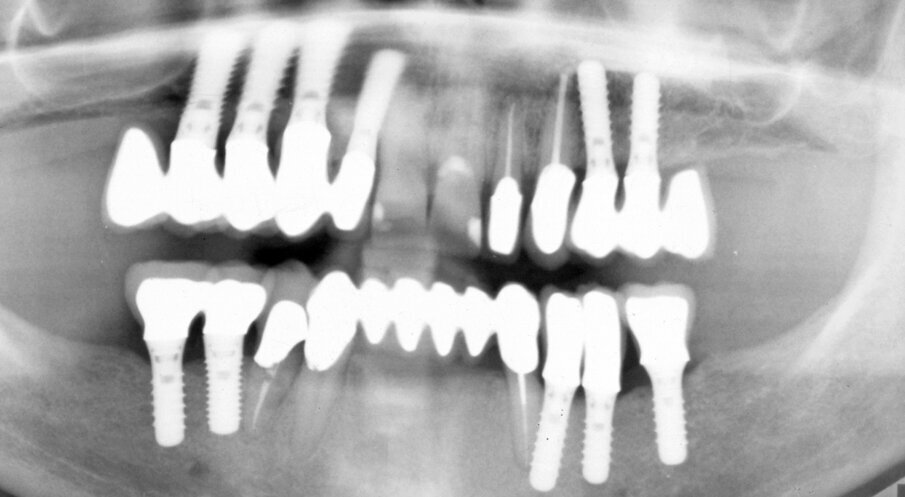

One year later, the patient presented again for consultation. Eleven implants have been placed (#12-15, 24, 25, 36-34, 45 and 46) and the maxilla and mandible have been restored with FPDs at the patient’s request (Fig. 3 – Fig. 5). However, the patient was dissatisfied with the esthetic results due to the unnatural length of the artificial teeth. Furthermore, the design of the existing FPDs impeded oral hygiene.

Fig. 3. 2nd consultation. Orthopantomograph. After implant placement and prosthetic treatment.